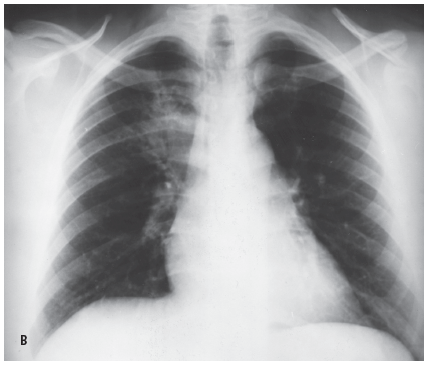

Radiologic evidence of a response to antibiotic therapy was absent in a 48-year-old man with “pneumonitis.” He had a productive cough with blood-streaked sputum, fever, fatigue, night sweats, and recent weight loss. The patient, a physician assistant, worked in a hospital and had recently been exposed to active tuberculosis; he had been a heavy smoker but had stopped smoking 20 years earlier. A chest radiograph (A) showed a paratracheal infiltrate (black arrows) in the right upper lobe that had increased in density in the 10 days since the previous radiograph (B) was obtained.

Blastomycosis can also masquerade as tuberculosis, as in the case of a 28-year-old man who had recently quit smoking and presented with a history of productive cough, mild hemoptysis, fatigue, fever, night sweats, and weight loss. A chest radiograph (C) showed disease process predominantly in the left upper lobe (white arrows) with infiltration as well as cavitation. A small area of infiltration is seen in the right hilar region. The clinical presentation and radiologic findings were consistent with tuberculosis. The patient failed to show clinical improvement with antibiotics, and a trial of antituberculous drug was started while results of sputum cultures were awaited. Twenty-six days after the patient’s initial visit, his chest radiograph (D) showed deterioration in both lungs. Sputum culture results were negative for Mycobacterium tuberculosis but positive for B dermatitidis. The patient was treated with ketoconazole; 2 months later, there was radiologic evidence of marked improvement.